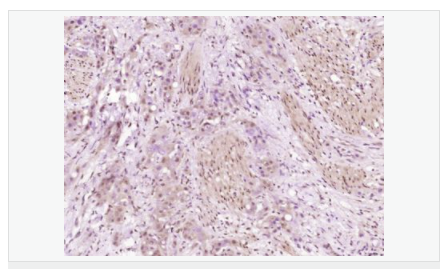

| 產品應用 | WB=1:500-2000 ELISA=1:5000-10000 IHC-P=1:100-500 IHC-F=1:100-500 ICC=1:100-500 IF=1:100-500 (石蠟切片需做抗原修復) not yet tested in other applications. optimal dilutions/concentrations should be determined by the end user. |

| 產品介紹 | Increase in fetal surfactant synthesis and lung maturity is caused by the glucocorticoidal induction of enzymes required for phosphatidylcholine synthesis towards the end of gestation (1). The regulation of gestational age-dependent induction of phosphatidylcholine synthesis by glucocorticoids is still unclear (1). The rate-controlling enzyme in the phosphatidylcholine biosynthetic pathway is CTP-phosphocholine cytidylyltransferase A (CCT A) (2–4). In cultured eukaryotic cells, this enzyme is essential for survival (3). The alpha isoform is located in the nucleus and is regulated by reversible phosphorylation and membrane association (3). There is significant identity between the alpha-helical membrane-binding domains of CCT A and soybean oleosin (2). Expressed CCT A has lipid-dependent cytidylyltransferase activity (5). The gene which encodes CCT A maps to human chromosome 3q (4). Function: Controls phosphatidylcholine synthesis. Subunit: Homodimer. Subcellular Location: Cytoplasm; cytosol. Membrane. It can interconvert between an inactive cytosolic form and an active membrane-bound form. Post-translational modifications: The serine residues of the C-terminus are phosphorylated. The inactive soluble form is stabilized by phosphorylation, the active membrane bound form is promoted by anionic lipids or diacylglycerol, and is stabilized by dephosphorylation. Similarity: Belongs to the cytidylyltransferase family. SWISS: P49585 Gene ID: 5130 Database links: Entrez Gene: 5130 Human Entrez Gene: 13026 Mouse Omim: 123695 Human SwissProt: P49585 Human SwissProt: P49586 Mouse Unigene: 135997 Human Unigene: 98775 Mouse Important Note: This product as supplied is intended for research use only, not for use in human, therapeutic or diagnostic applications. |